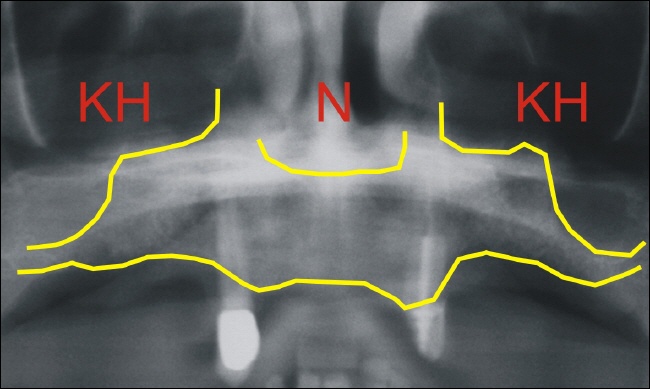

Das Röntgenbild zeigt die geringe Knochenhöhe im Seitenzahnbereich. Die untere gelbe Linie entspricht dem knöchernen Kieferkamm. Die gelbe Linie darüber entspricht dem knöchernen Boden der Kieferhöhle (KH). Im mittleren Bereich ist der knöcherne Nasenboden (N) als gelbe Linie eingezeichnet.

Rechts und links auf dem Röntgenbild sind nur wenige Millimeter zwischen den gelben Linien, das bedeutet, es ist primär nicht ausreichend Knochenhöhe für eine Implantation vorhanden, der fehlende Knochen muss aufgebaut werden.